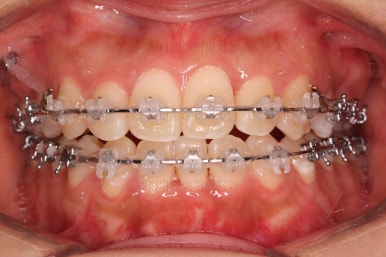

초진 시 입안의 모습입니다.

그냥 봐도 뭔가 애매함이 있죠?

중앙선이 맞지 않고, 교합이 떠보이는 양상이네요.

윗니는 좌측 작은 어금니가 한 개 모자랐고 아랫니는 앞니 하나가 모자라네요.

그런데 앞니는 아랫니가 1개 모자란 채로 교합이 맞춰져서 윗니가 하나 부족한 채로 애매한 상태였어요.